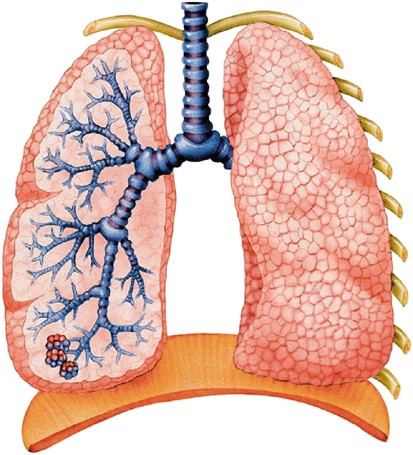

Здоровье дыхательной системы: бронхи и легкие